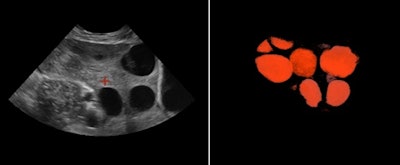

Uterus shape visualized with 3D thick-slice image (left) and 3D volume (right). All images courtesy of ContextVision.In reproductive medicine, the ovaries are measured to detect abnormalities. Ovarian size can be determined by measuring the ovary in three dimensions (width, length, and depth) on views in two orthogonal planes or by visualizing a 3D volume, according to the 2008 AIUM practice parameter "Ultrasound in Reproductive Medicine."

Follicles in the ovary evaluated on B-plane image of the ovaries (left). Inversion rendering (right) clearly shows the total number of follicles in the ovary.In obstetrics, it has been shown that volumetric ultrasound and 3D visualization have helped to define fetal surfaces and assess fetal facial abnormalities, according to Dr. Anders Selbing, PhD, of Linköping University in Sweden. Automated measurements of nuchal translucency with 3D ultrasound have also been developed.